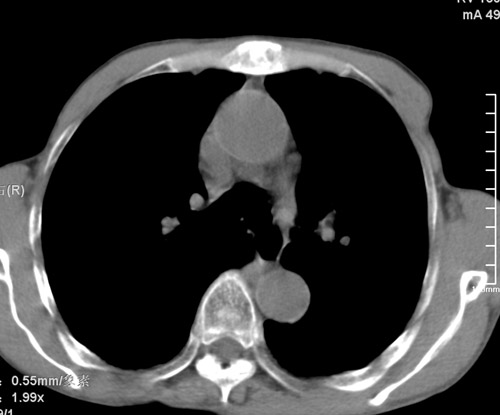

标题: CT17529:男 76 胸背部不适半月 胸透支气管炎 行CT检查 [打印本页]

标题: CT17529:男 76 胸背部不适半月 胸透支气管炎 行CT检查

意见 老年肺 少许炎症 肺大泡 右肺门略大 但支气管通畅  请各位高手指教如何下意见

支持楼主意见,右肺门略大,可能为肺动脉增粗.

慢支肺气肿,肺动脉高压.